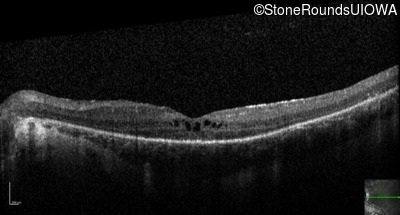

Optical Coherence Tomography - Left - 20/50

Exemplar / OCT Stack